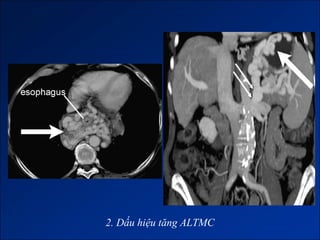

Dấu hiệu tăng ALTMC

2. Dấu hiệu tăng ALTMC